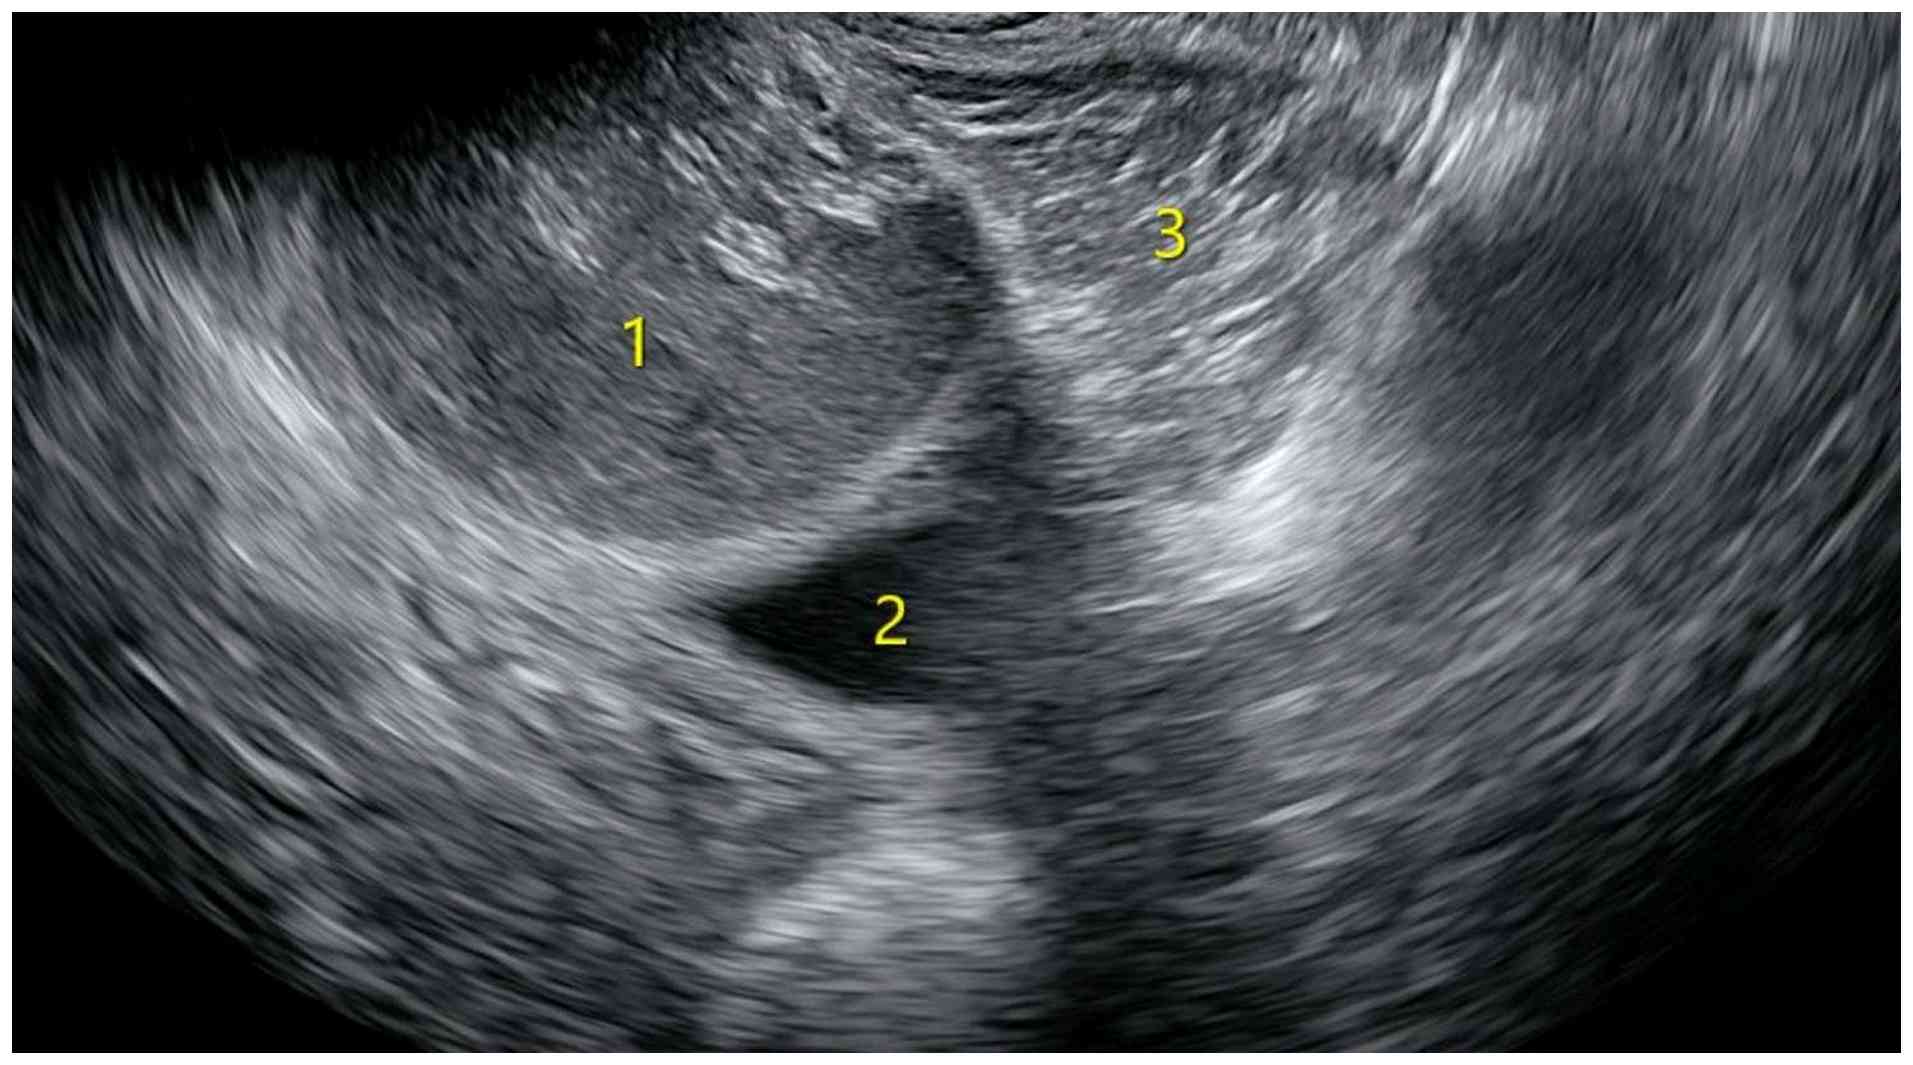

A 32-year-old previously healthy female presented to the First People's Hospital of Xiaoshan District (Hangzhou, China) in September 2024 with unexplained abdominal pain, which was the first occurrence of such symptoms within the preceding 2 months. The patient exhibited no signs of intestinal dysfunction or symptoms indicative of urinary tract irritation. Notably, a digital rectal examination revealed a solid, fixed mass located on the posterolateral wall of the rectum. Gynecological ultrasound prior to surgery revealed two unevenly strong echo masses in the pelvic cavity that were located posterior to the cervix and lateral to the rectum (Fig. 1). The larger mass measured ~8.0x6.5x6.1 cm, whereas the second largest measured ~6.4x6.0x4.8 cm. Both masses had clear boundaries and regular shapes, with no obvious blood flow signals detected. MRI revealed two abnormal signal shadows in the perirectal and bilateral rectal fossa. The larger shadow measured ~53x81 mm, with a clear boundary and smooth edges. The cyst fluid exhibited low signal intensity on T1-weighted imaging (T1WI), and high signal intensity on T2WI (Fig. 2). The internal signal was slightly mixed, with pronounced high signal intensity on diffusion-weighted imaging (DWI) and low signal intensity on apparent diffusion coefficient (ADC) mapping. No enhancement within the cyst was observed after contrast administration. A circular low signal intensity was visible on T2WI in the cyst wall, which was moderately enhanced after contrast administration.

Ultrasonography shows two

heterogeneous hyperechoic masses. The numeral 1 indicates the

larger mass, numeral 2 depicts a hypoechoic liquid region, and

numeral 3 denotes the smaller mass.

Figure 1

Ultrasonography shows two heterogeneous hyperechoic masses. The numeral 1 indicates the larger mass, numeral 2 depicts a hypoechoic liquid region, and numeral 3 denotes the smaller mass.